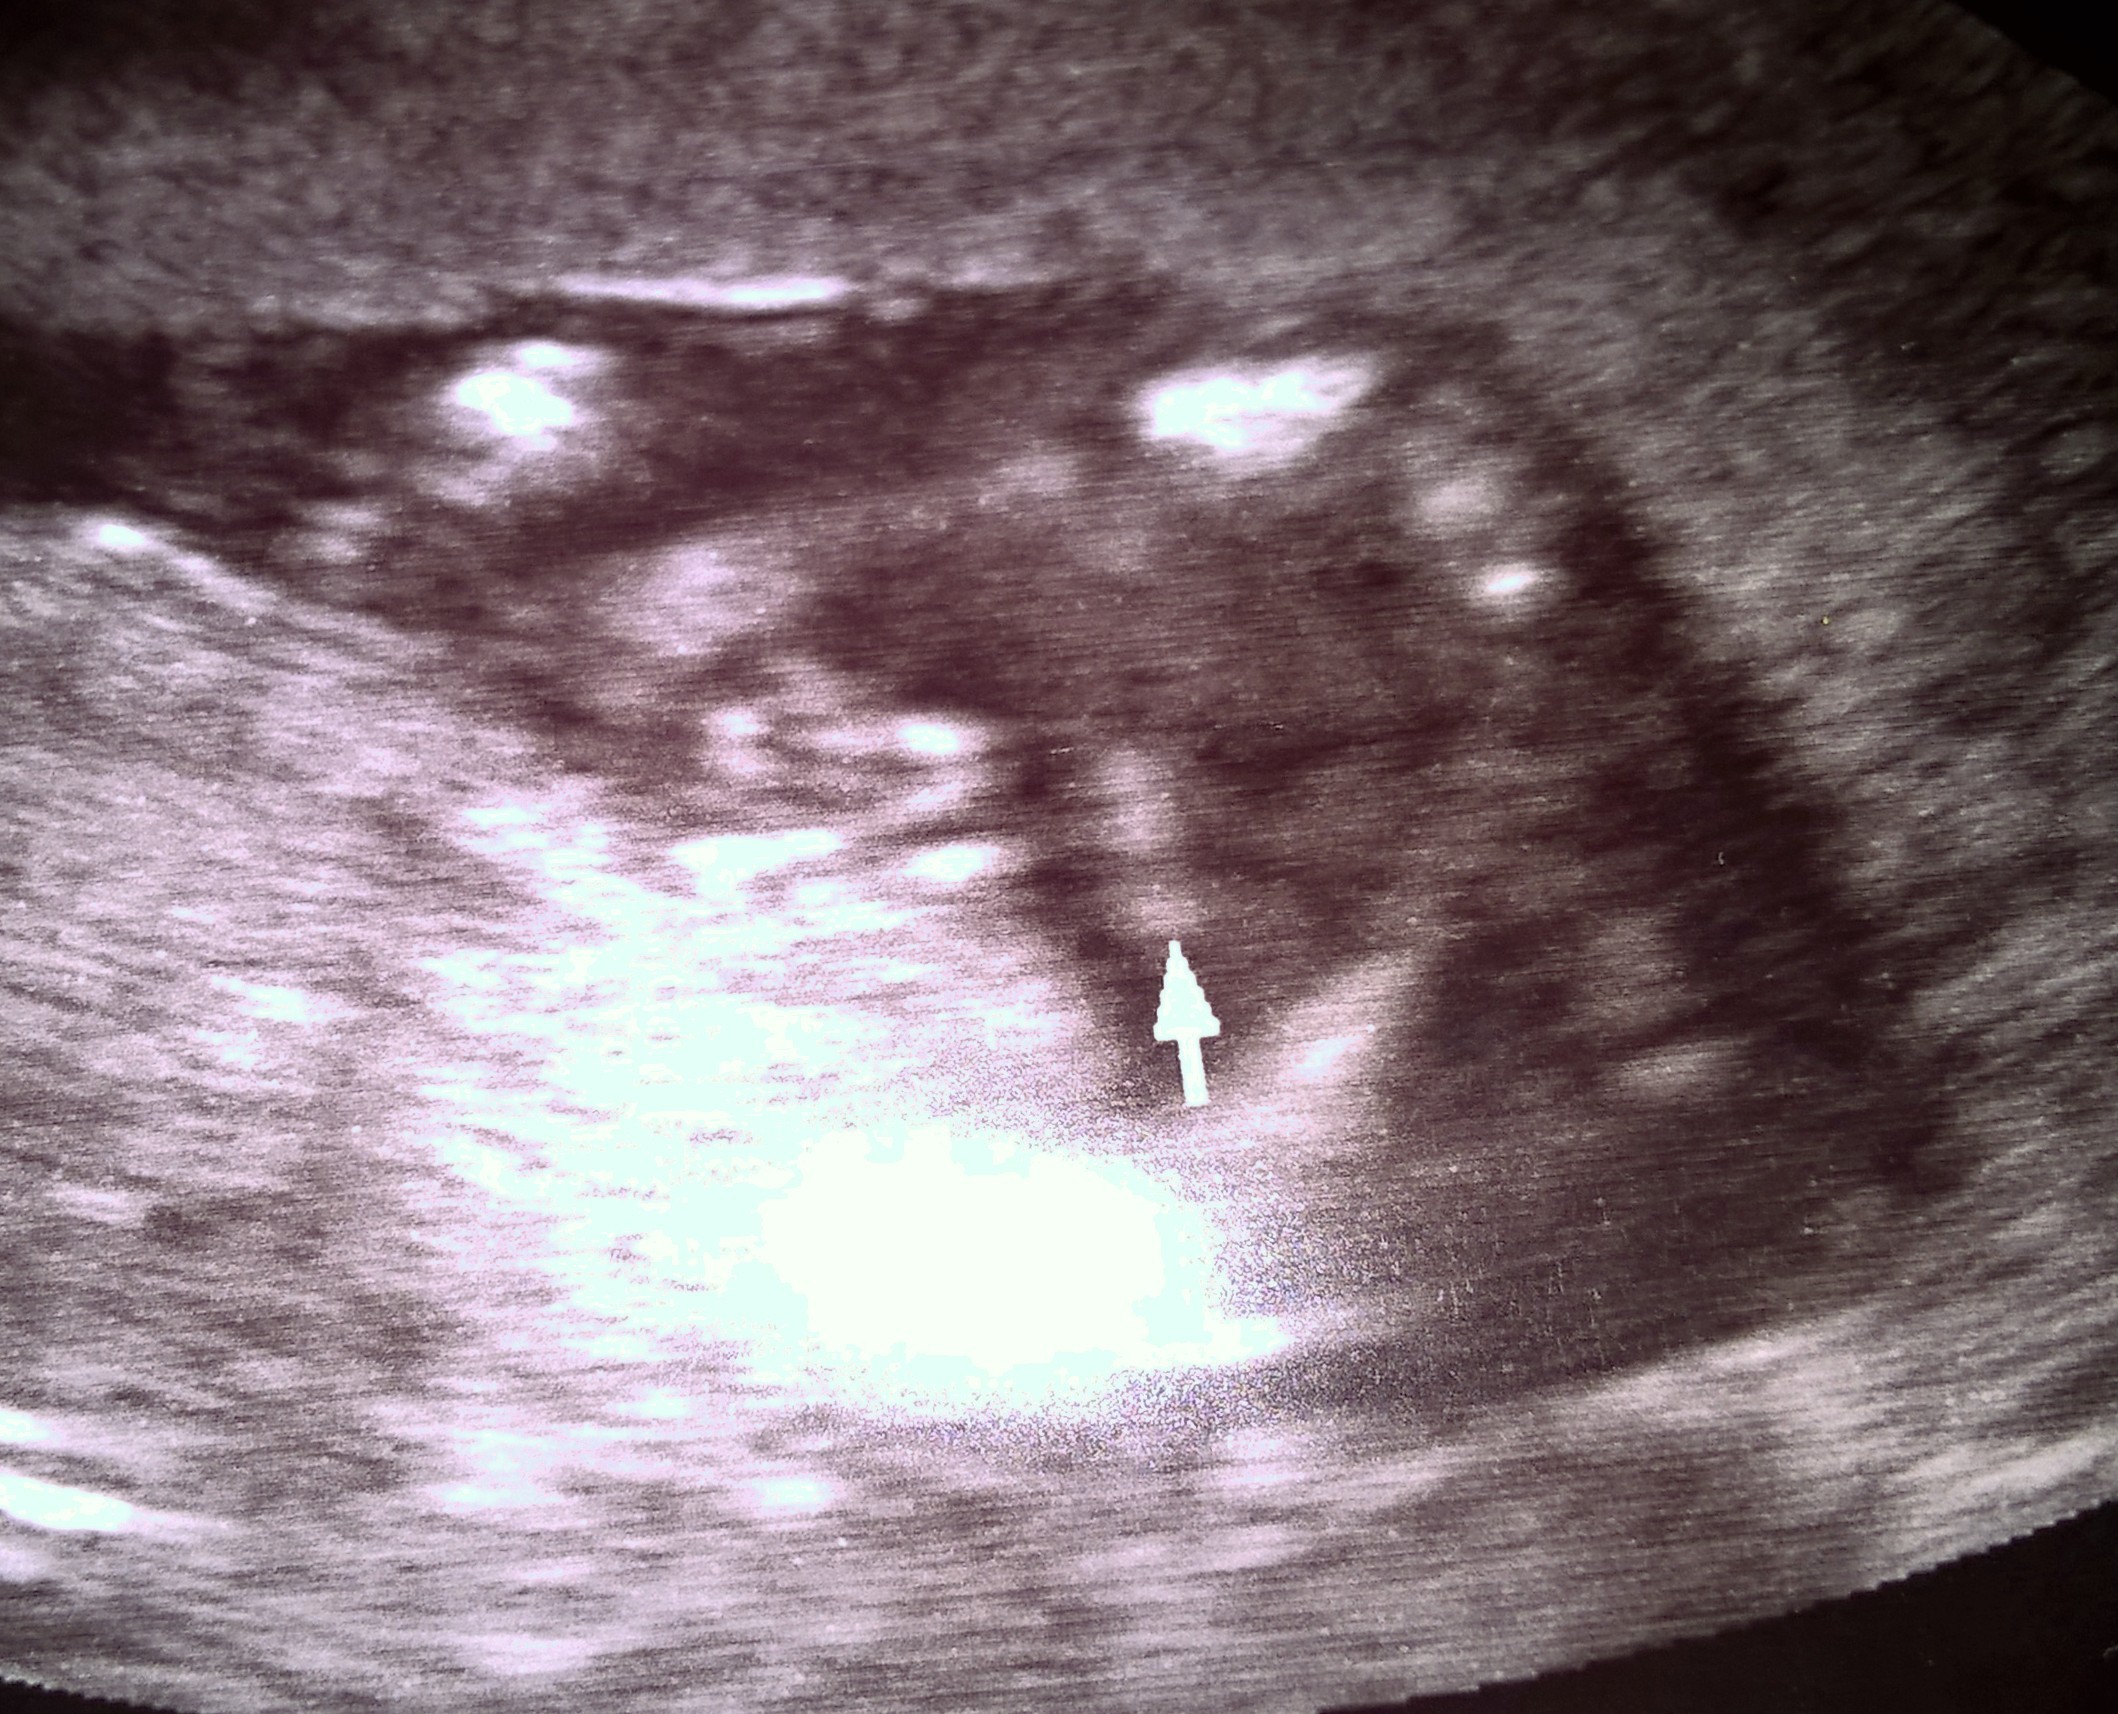

Ana-Racja pokazuj usg! Ale jak 3 kreski to laska jak nic

Ana choć nie jestem ekspertem w tej dziedzinie ale jak na moje oko to synka z tego nie będzie ;-)